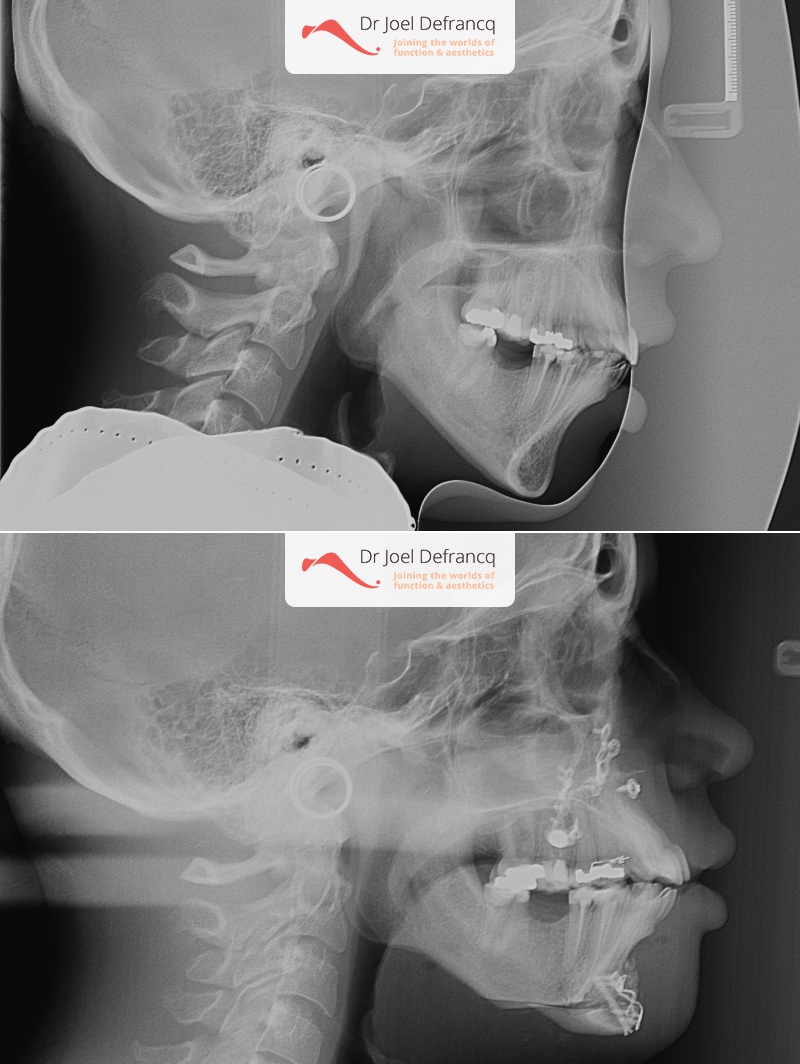

Diagnose van het gezicht

- Te kleine onderkaak (Overbeet)

- Te lange bovenkaak

- Te smalle bovenkaak

- Vertikale verkorting bovenkaak (Le Fort I)

- Kinchirurgie